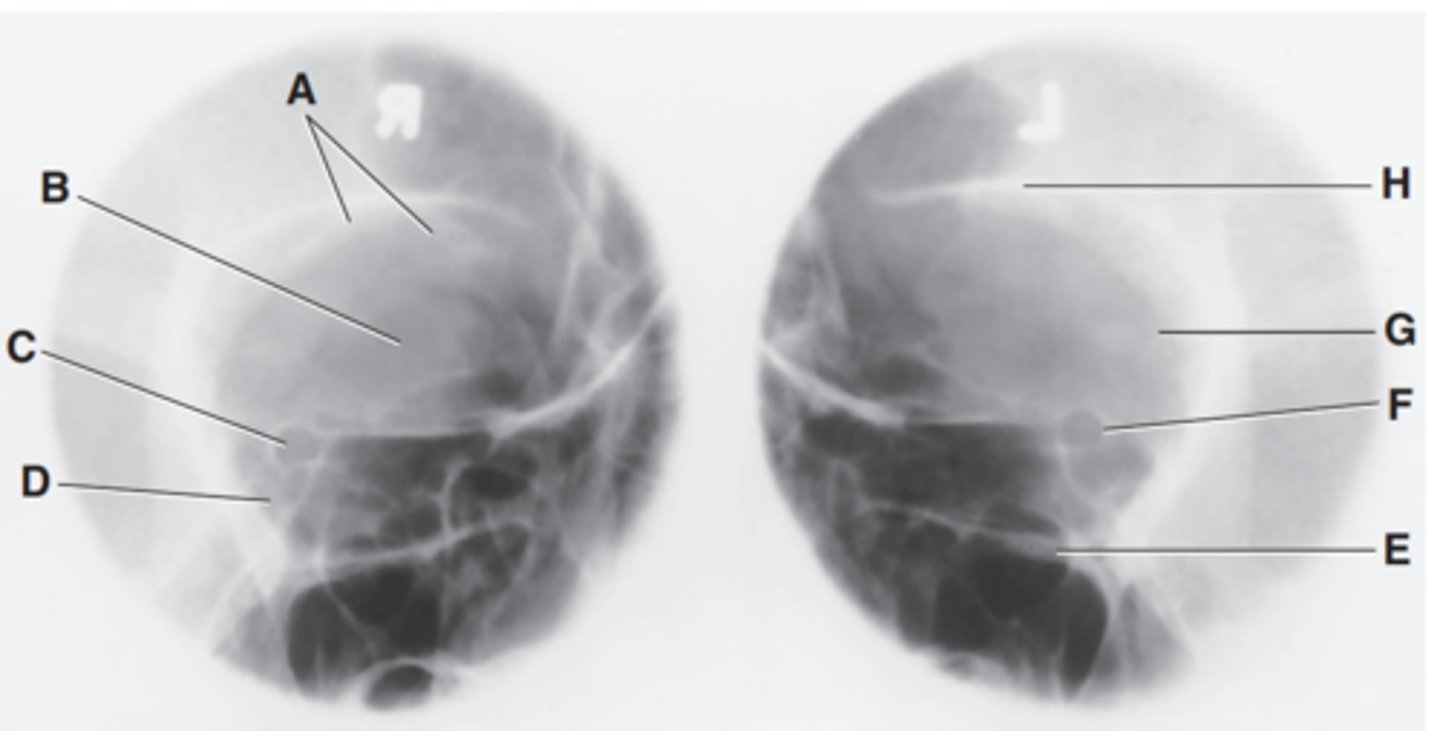

EAM

Label A

Mastoid portion of temporal bone

Label B

Occipital bone

Label C

Lambdoidal suture

Label D

Clivus

Label E

Dorsum sellae

Label F

Posterior clinoid processes

Label G

Anterior clinoid processes

Label H

Vertex of cranium

Label I

Coronal suture

Label J

Frontal bone

Label K

Orbital plates

label L

Cribriform plate

Label M

Sella turcica

Label N

Body of sphenoid (sphenoid sinus)

Label O

Petrous portion of temporal bone

Label P